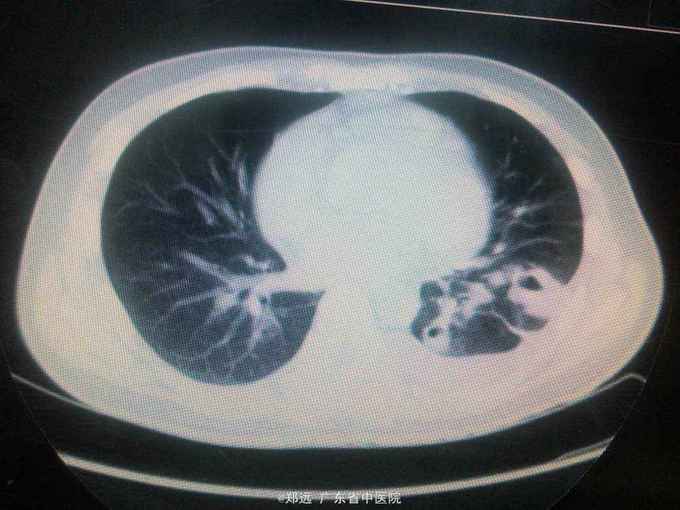

体查:双下肺湿啰音。三尖瓣区3/6级收缩期杂音。 胸部ct:双肺斑片结节影并空洞形成,左胸少量积液。血色素88克/升,白细胞11.48,中性粒81.3%,降钙素原14.84,ALT 121,AST 134.超声提示三尖瓣赘生物,三尖瓣大量返流。血培养金葡菌。

诊断:急性感染性心内膜炎,脓毒症,肺脓肿,丙型肝炎。 治疗:入院予万古霉素0.5克q6h,经治疗五日血象正常,降钙素原1.54,但仍反复高热,考虑肺脓肿合并阴性菌感染,加用头孢哌酮舒巴坦3克q12h,治疗五日仍有发热,血培养阴性,白细胞正常,降钙素原0.15,头孢哌酮舒巴坦改为美罗培南0.5克q8h,两日后无再发热,维持该方案至治疗四周后改予万古霉素0.5克q8h加美罗培南0.5克q12h继续治疗两周,复查超声提示三尖瓣熬生物较入院时缩小约三分之一,多次血培养阴性,胸部ct提示肺部炎症明显吸收予出院。出院后患者仍间发热,出院后约七周再次返院,查白细胞13.88,中性粒65.9%,血色素正常,降钙素原0.55,血培养提示溶血葡萄球菌,胸部ct示双肺多发感染灶,较前吸收,胸腔积液已吸收。予原万古霉素加美罗培南方案治疗,两日后无发热,治疗三周后多次血培养阴性,胸部ct提示肺部感染基本吸收,行三尖瓣赘生物切除并三尖瓣修补术,术中见三尖瓣后瓣瓣叶破坏严重,赘生物大小约2*1厘米。术后恢复良好,维持万古霉素加美罗培南治疗一周后改予万古霉素0.5克q8h加阿米卡星0.4克q12h治疗两周,赘生物及多次血培养阴性予出院。